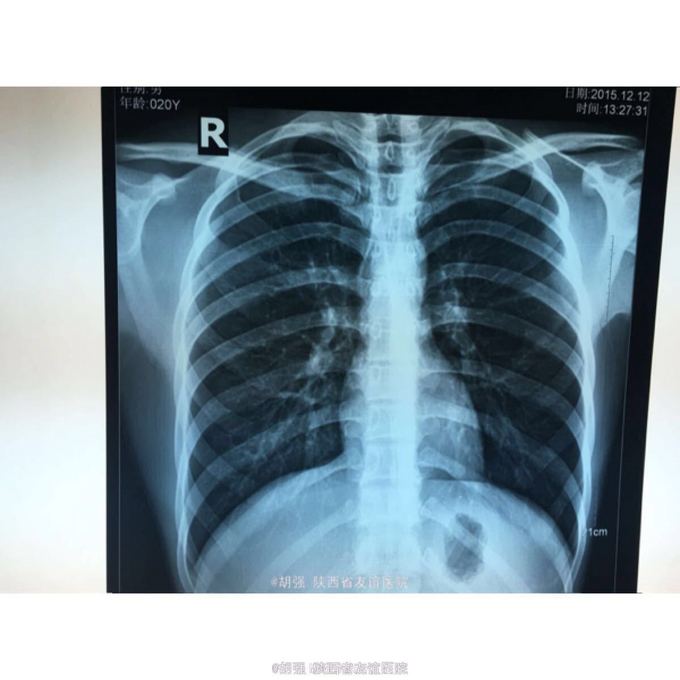

查体:口唇无发绀,咽充血,双侧扁桃体2度大,表面可见脓胎。两肺呼吸音粗糙,可闻及管状呼吸音。余查体无明显异常。 辅助检查:血常规提示白细胞及血小板明显低于正常值,肝功提示转氨酶升高。凝血系列:PT、APTT时间明显延长。T sport试验弱阳性。10月份胸部CT平扫未见明显异常。10月26日及12月12日胸片未见明显异常。12月19日胸部CT提示:两肺斑片状阴影,两侧胸腔积液。